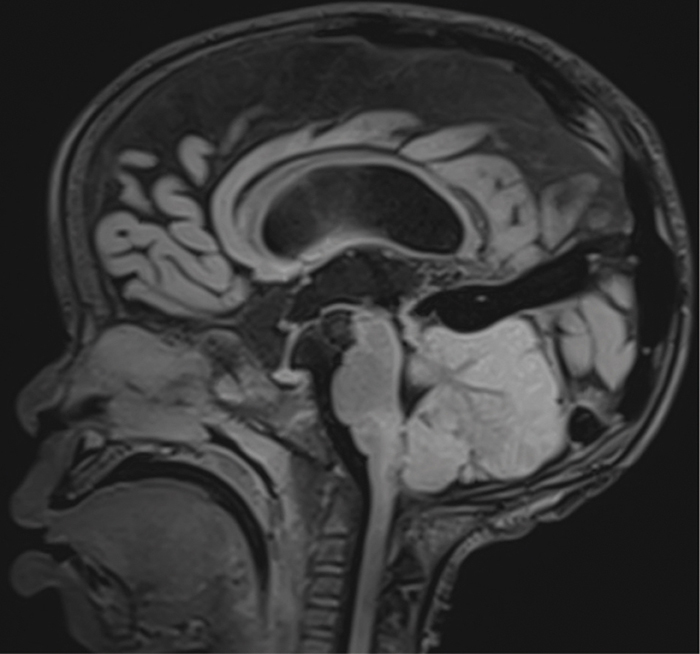

We report the case of a 4‑year‑old child who experienced rapid neurological decline following opioid administration during anesthesia for an interventional procedure to treat a vein of Galen aneurysm. Cerebral magnetic resonance imaging (MRI) revealed marked cytotoxic edema in both cerebellar hemispheres and the brainstem, indicative of opioid‑induced neurotoxicity. A follow‑up MRI, performed 2 weeks later, showed profound cerebellar and brainstem atrophy and showed reduction in mass effect due to cytotoxic edema. Teaching point: Pediatric opioid‑use‑associated neurotoxicity with cerebellar edema (POUNCE) syndrome is a rare condition, characterized by cerebellar edema as a hallmark feature, which can be identified on MRI in pediatric patients following opioid use.

Abstract Image